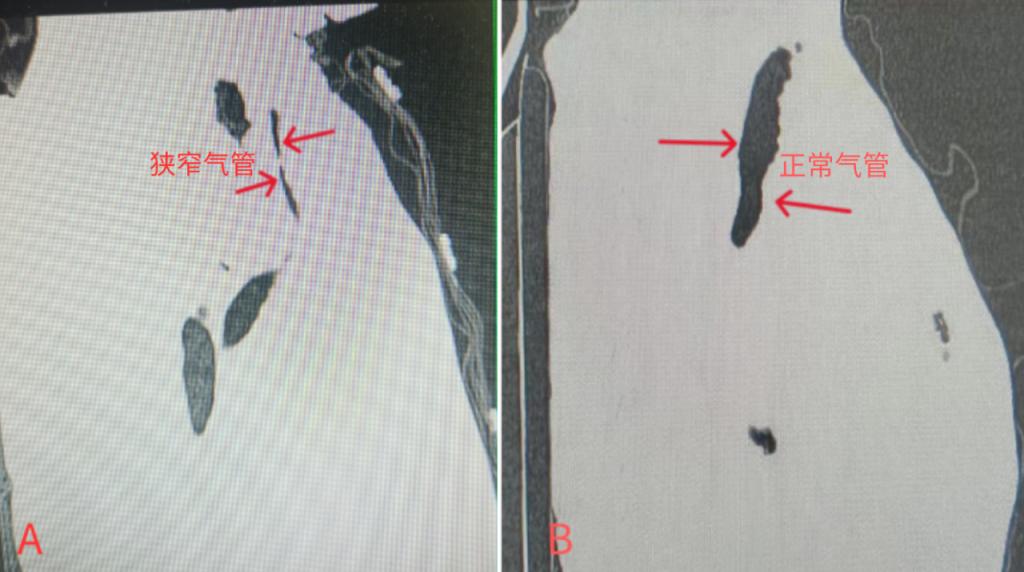

A:术前CT矢状位上,仲婆婆因肿瘤受压极度狭窄的气管(箭头处);

B:矢状位上,正常人通畅的气管(箭头处)